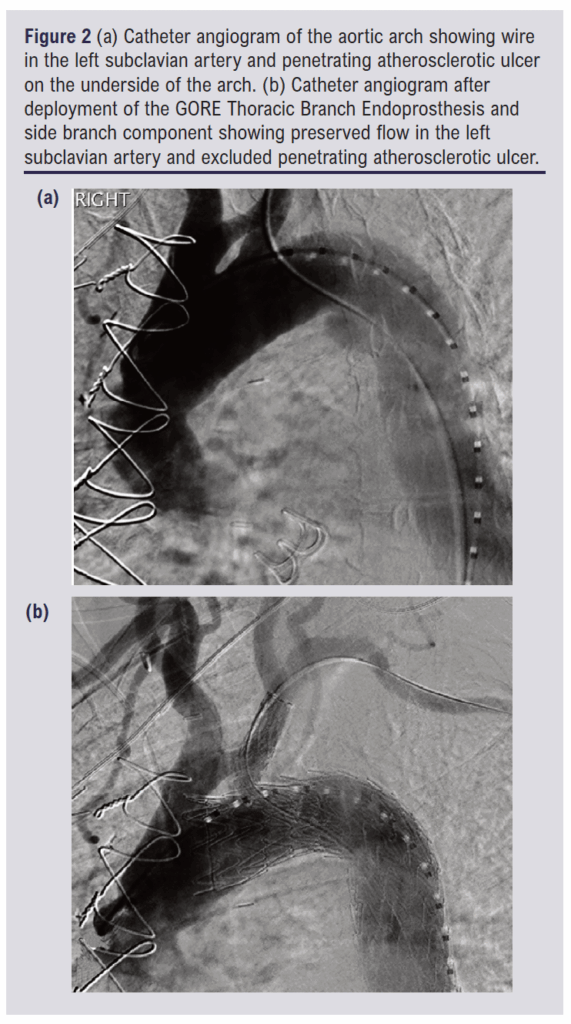

Angled angiography was performed to delineate the left SCA. A 31 mm calibre TBE with an 8 mm internal portal was inserted over the Lunderquist and Terumo wires and advanced to line up the portal markers with the SCA. There was mild wire wrap which was relieved using the simple measure of retracting the device to the descending aorta, turning it and re-advancing it. This was only required once. With the TBE in place, it was deployed by one operator while the second operator fixed the delivery system at the hub of the DRYSEAL sheath. A 12 mm calibre, 60 mm length side branch component was then inserted from the femoral side of the Terumo wire while the Vanschie catheter was inserted from the brachial side of the Terumo wire. With these two devices tip-to-tip, the side branch component was advanced into the portal and then the SCA and deployed. A 10 x 20 mm Advance 35LP Low-Profile PTA Balloon Dilatation Catheter (Cook Medical) was advanced from the femoral access. The portal overlap was ballooned first, then the distal end of the side branch component, then the middle, as per the manufacturer’s recommendations. No ballooning of the TBE was performed. Angiography was repeated, confirming exclusion of the PAU and patency of the left SCA branch. Pre- and post-deployment angiograms are shown in Figure 2. The anaesthetic chart records the procedure as commencing at 11:55 and finishing at 12:50.